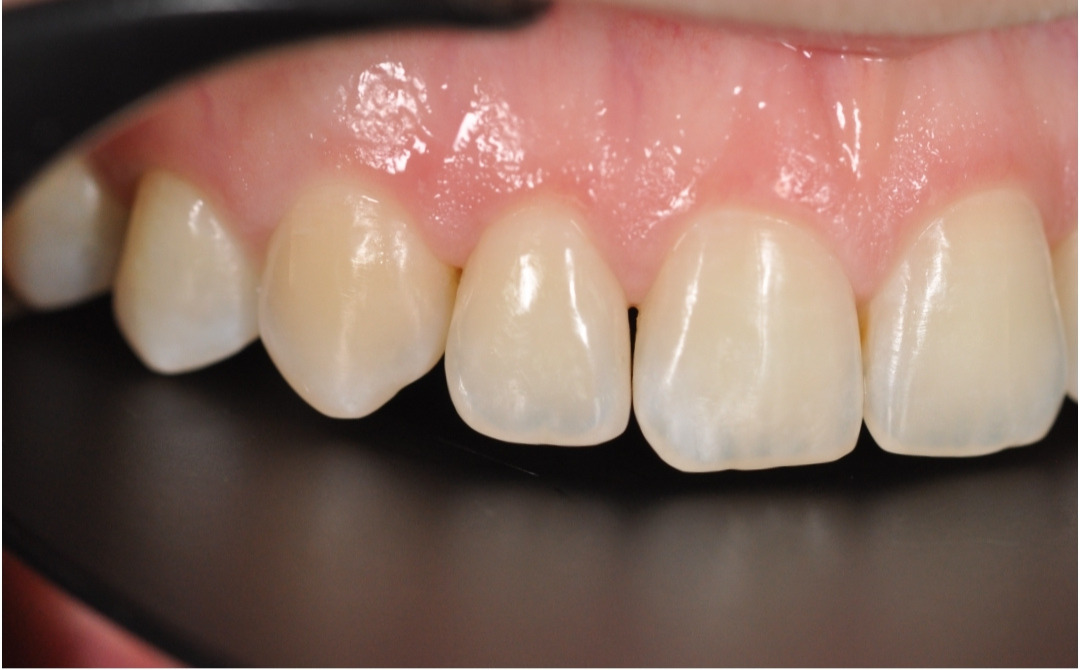

После

После снятия брекет-системы стоматолог-терапевт провела художественную реставрацию формы боковых резцов, добившись идеальной гармонии и естественности улыбки.

Эстетика

Исправлен прямой прикус, восстановлена форма резцов, а улыбка стала не только красивой, но и здоровой с точки зрения биомеханики.